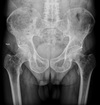

Give a list of differentials in order from most to least likely.

1. Chondrosarcoma (large calcified soft tissue mass) 2. Enchondroma 3. Infarct